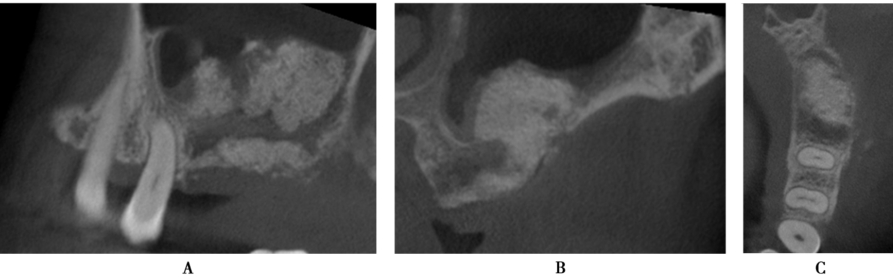

术前CBCT显示缺牙区牙槽嵴顶到上颌窦底的最小高度约3mm,上颌窦底黏膜约1mm,上颌窦腔影像清澈,无炎症,侧壁厚度1~2mm(图12)。

图12 术前CBCTA.冠状面;B.矢状面